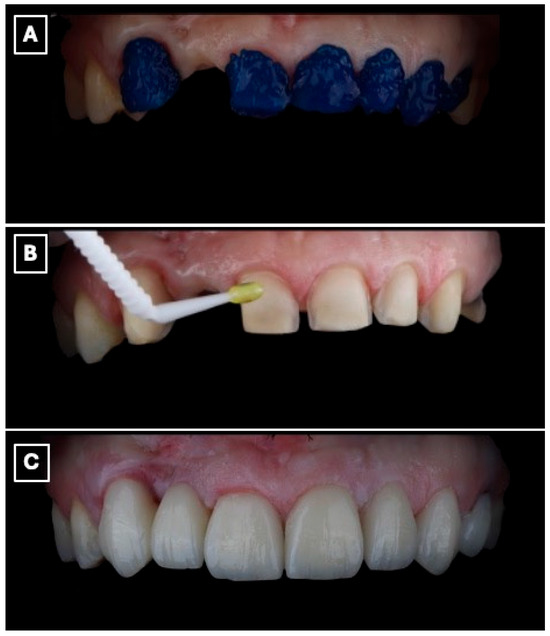

A silicone putty index (Express™ STD Putty, 3M ESPE, St. Paul, MN, USA) was fabricated from the printed diagnostic wax-up, and an intraoral mock-up was performed using a bis-acryl provisional material (Protemp™ 4, 3M ESPE, St. Paul, MN, USA) (Figure 3A). The mock-up enabled clinical evaluation of tooth proportions, incisal edge position, and smile integration, and served as a communication tool to confirm esthetic acceptance with the patient before performing any irreversible procedures.

Figure 3.

Digital wax-up used for esthetic analysis and prosthetic planning of the anterior rehabilitation. (A) Virtual representation of the maxillary anterior region before wax-up, serving as a baseline for evaluating tooth position, incisal edge discrepancies, and space availability for the planned resin-bonded fixed dental prosthesis. (B) Digital wax-up design illustrating the proposed single-retainer cantilever resin-bonded fixed dental prosthesis and laminate veneers, with idealized tooth proportions, incisal edge position, and symmetry used to guide enamel-confined tooth preparation, pontic emergence profile, and overall esthetic integration within the smile.

Tooth preparation was performed under mock-up guidance to ensure minimal enamel reduction and to create optimal enamel-bonding surfaces (Figure 3B). Final impressions were obtained using a polyvinyl siloxane impression material (Imprint™ 4 PVS, 3M ESPE, St. Paul, MN, USA) and submitted to the dental laboratory for definitive fabrication.

Beyond its role in visualization, the digital wax-up and intraoral mock-up contributed directly to clinical decision-making and execution. The digitally planned wax-up enabled precise control of tooth proportions, incisal edge position, and pontic emergence profile, facilitating enamel-confined preparation and preservation of sound tooth structure. The intraoral mock-up functioned as a reduction guide during tooth preparation, minimizing unnecessary enamel removal and reducing chairside adjustments at the time of prosthesis seating. This digital-to-clinical transfer enhanced treatment predictability by allowing preoperative verification of esthetics and function, thereby improving clinical efficiency and patient acceptance.

The enamel surface of the abutment tooth was selectively conditioned using 37% phosphoric acid gel (Total Etch, Ivoclar Vivadent, Schaan, Liechtenstein), followed by rinsing and controlled air-drying to maintain an enamel-restricted bonding substrate. A universal adhesive system (Adhese Universal, Ivoclar Vivadent, Schaan, Liechtenstein) was then applied according to the manufacturer’s recommendations. Cementation of the resin-bonded fixed dental prosthesis was performed using a light-cured resin cement (Variolink Esthetic LC, Ivoclar Vivadent, Schaan, Liechtenstein), with polymerization from multiple orientations to ensure adequate curing at the enamel-ceramic interface (Figure 6A–C). Excess cement was removed during the elastic phase, and occlusal refinement was subsequently carried out to eliminate static, functional, and excursive contacts on the pontic and retainer, thereby limiting mechanical loading on the cantilever restoration (Figure 6C).

Figure 6.

Adhesive cementation of the lithium disilicate single-retainer cantilever resin-bonded fixed dental prosthesis using a light-cured resin cement. (A) Intraoral try-in and seating of the prosthesis prior to polymerization, confirming complete seating of the cantilever retainer, passive adaptation at the adhesive interface, and absence of premature contacts that could induce tensile or shear stresses. (B) Removal of excess resin cement during the gel phase following initial light activation, a critical step to prevent marginal overhangs, reduce plaque retention, and minimize the risk of gingival inflammation or marginal discoloration at the enamel-ceramic interface. (C) Final intraoral view after complete polymerization, demonstrating stable marginal adaptation, controlled occlusal scheme with elimination of functional contacts on the pontic, and harmonious esthetic integration of the restoration within the anterior smile zone, which are essential factors for long-term clinical success of cantilever resin-bonded prostheses.